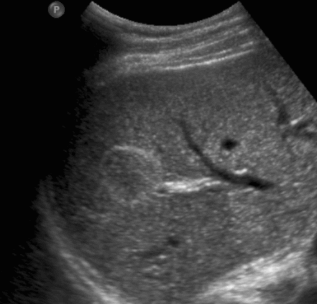

2~3cm hcc sono features ③ 3~5 cm hcc sono finding

- hypo-hyperechoic

- heterogenous

- irregular

- hump sign (표면에 존재하는 결절형 종괴에서 간표면으로 종괴가 돌출하는 경우 나타난다)

- mosaic pattern (종양내부에 괴사나 출혈이 생겨 내부에 균열이 있는 것처럼 보이는 모자이크패턴이 나타남)

- color doppler : internal mass pattern (feeding artery)